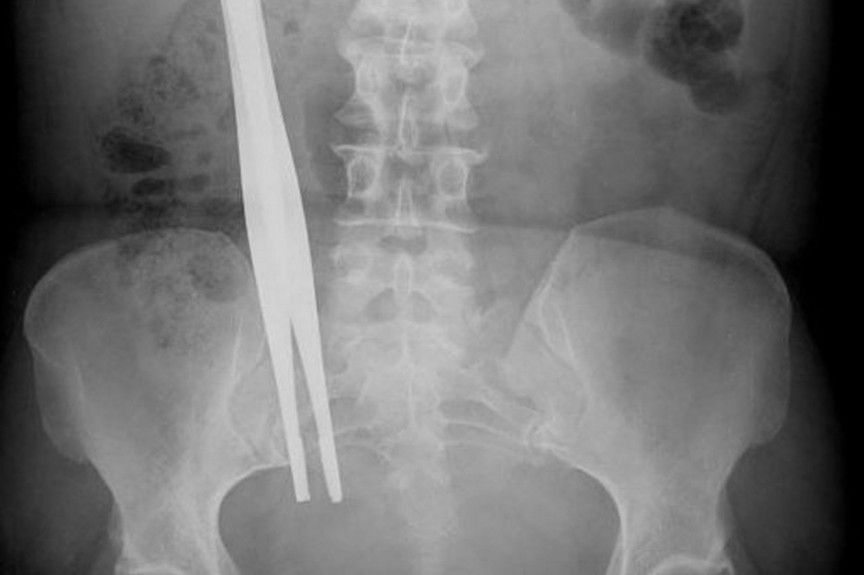

Неопределенные инородные предметы.

Как ни странно, посторонние предметы в теле остаются чаще всего именно после операций. Это может все, что угодно: зажимы, скальпели, вата, трубки и даже наручные часы. Исследование показало, что такие инциденты случаются в неделю 39 раз.

Ленни Леклер вплотную столкнулась с врачебной халатностью, когда появились усложнения после проведенной операции на кишечнике. Тяжелые симптомы указывали, что болезнь прогрессировала и её направили на МРТ. Сканирование показало, что в её кишечнике врачи оставили губки. Она перенесла несколько дополнительных операций, разок впала в кому, а теперь к ней прикреплен калоприемник.